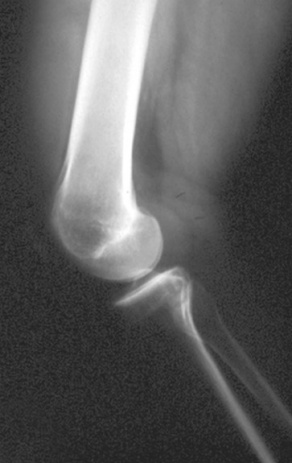

PVNS